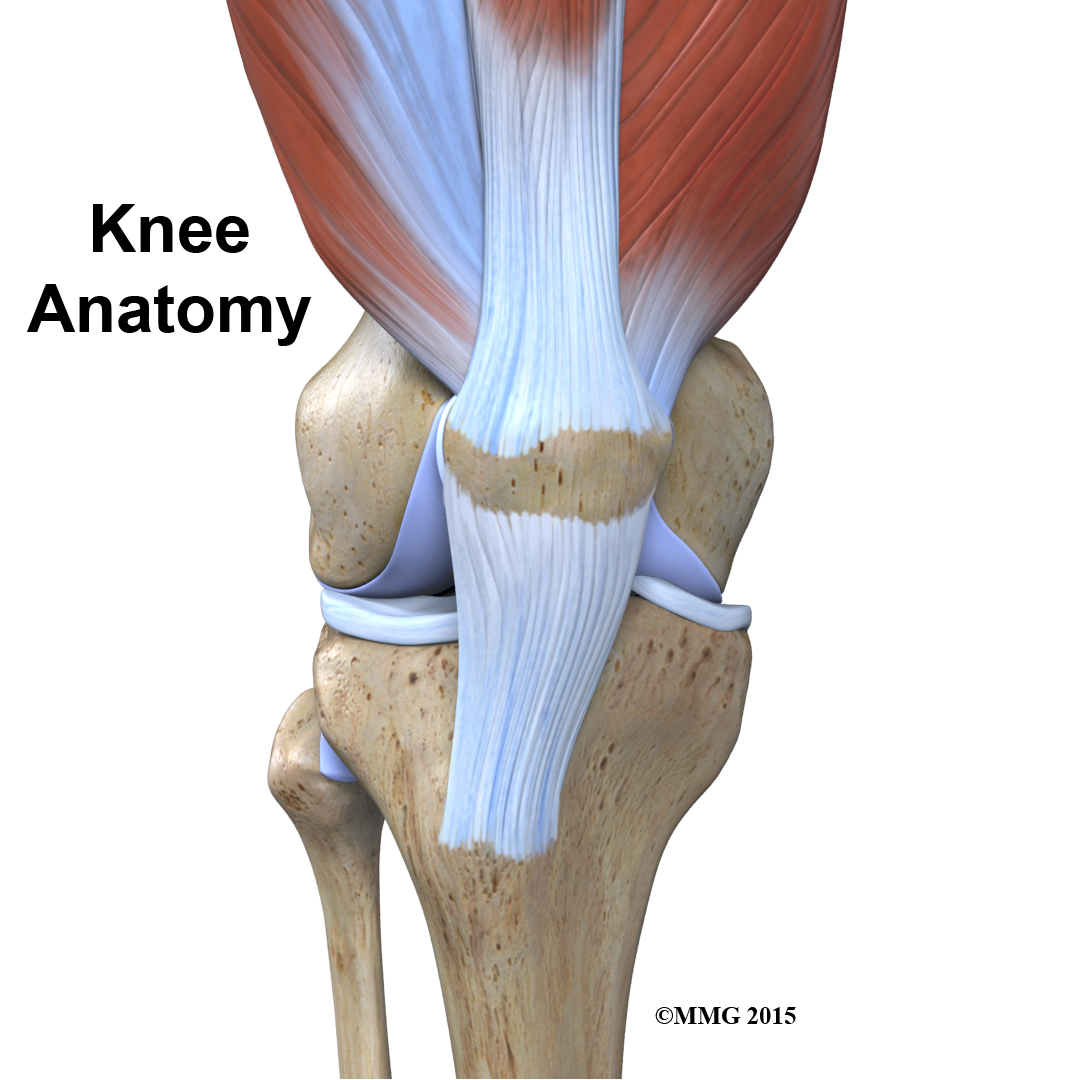

To better understand how knee problems occur, it is important to understand some of the anatomy of the knee joint and how the parts of the knee work together to maintain normal function.

The knee is the meeting place of two important bones in the leg, the femur (the thighbone) and the tibia (the shinbone). The patella (or kneecap, as it is commonly called) is made of bone and sits in front of the knee.

The knee joint is a synovial joint. are enclosed by a ligament capsule and contain a fluid, called synovial fluid, that lubricates the joint.

The end of the femur joins the top of the tibia to create the knee joint. Two round knobs called femoral condyles are found on the end of the femur. These condyles rest on the top surface of the tibia. This surface is called the tibial plateau. The outside half (farthest away from the other knee) is called the lateral tibial plateau, and the inside half (closest to the other knee) is called the medial tibial plateau. The patella glides through a special groove formed by the two femoral condyles called the patellofemoral groove.

Tendons are similar to ligaments, except that tendons attach muscles to bones. The largest tendon around the knee is the patellar tendon. This tendon connects the patella (kneecap) to the tibia. This tendon covers the patella and continues up the thigh.

There it is called the quadriceps tendon since it attaches to the quadriceps muscles in the front of the thigh. The hamstring muscles on the back of the leg also have tendons that attach in different places around the knee joint. These tendons are sometimes used as tendon grafts to replace torn ligaments in the knee.

The extensor mechanism is the motor that drives the knee joint and allows us to walk. It sits in front of the knee joint and is made up of the patella, the patellar tendon, the quadriceps tendon, and the quadriceps muscles. The four quadriceps muscles in front of the thigh are the muscles that attach to the quadriceps tendon. When these muscles contract, they straighten the knee joint, such as when you get up from a squatting position.

The way in which the kneecap fits into the patellofemoral groove on the front of the femur and slides as the knee bends can affect the overall function of the knee. The patella works like a fulcrum, increasing the force exerted by the quadriceps muscles as the knee straightens. When the quadriceps muscles contract, the knee straightens.